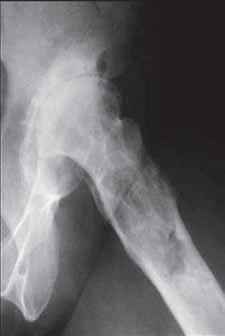

b

Rycina 14.2. Osteokondukcyjne pobudzenie zrostu kostnego belką i przeszczepami kości allogenicznej złamania okołoprotezowego kości udowej lewej po realoplastyce rewizyjnej stawu kolanowego; a) rentgenogram w projekcji przednio-tylnej (a-p), b) rentgenogram w projekcji bocznej (l).